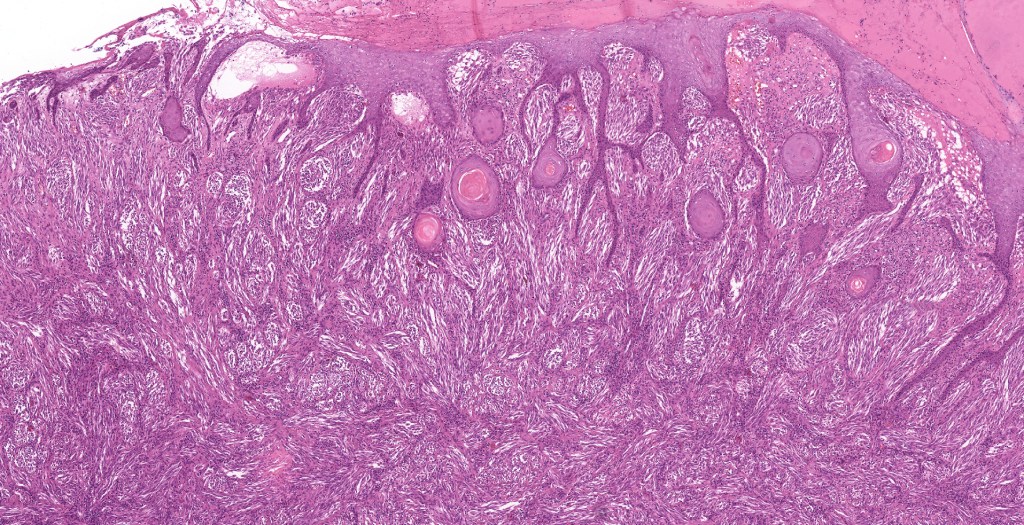

•Hyperkeratosis & acanthosis, sometimes very marked

•Pseudoepitheliomatous hyperplasia

•Superficial vascular ectasia very frequently present

•Junctional nests often vertically orientated, dyscohesive with a surrounding retraction artifact

•Pleomorphism is almost invariable but affects all of the population to the same extent i.e., the cells & nuclei all look very much the same

•Spindle cell nests often display a “raining down” growth pattern

•Kamino bodies (often multiple) are a characteristic feature